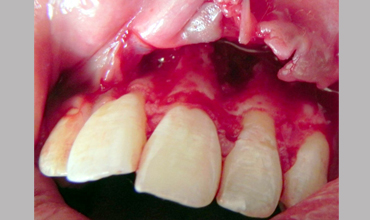

Periapical Surgery

Surgical Management Of Large Periapical Cyst